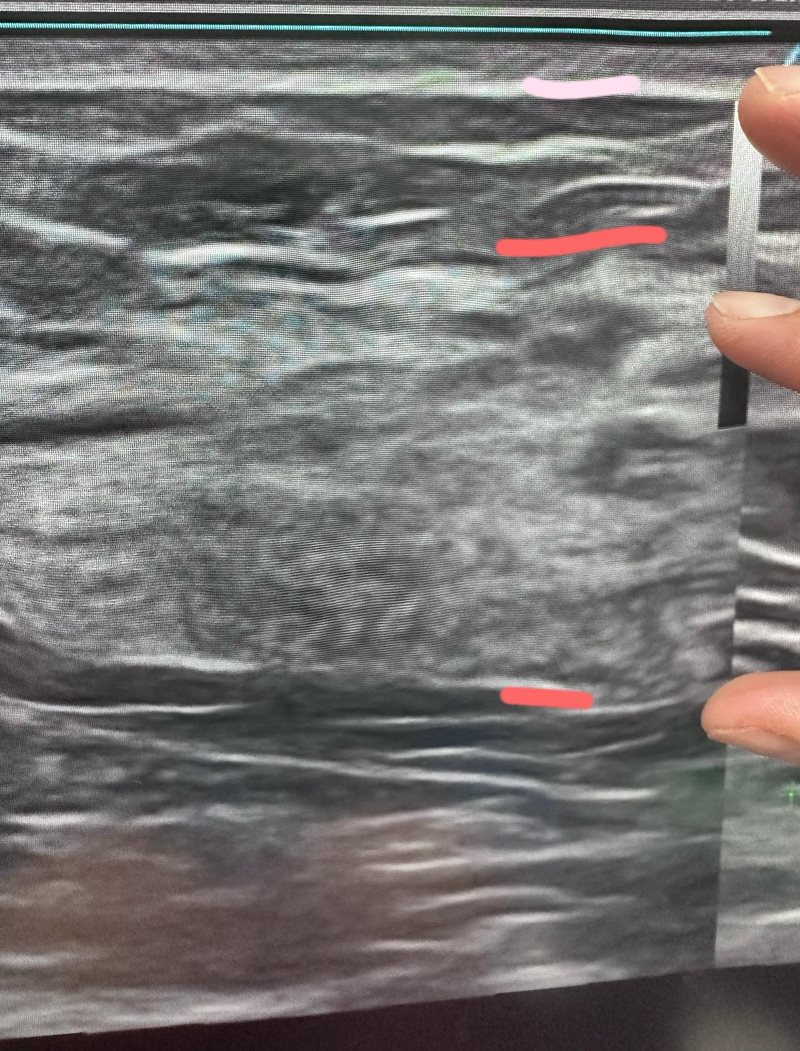

โดยหญิงสาวได้โพสต์ภาพเอกซเรย์เต้านมผ่านอินสตาแกรม พร้อมบอกว่า "หลายคนอยากเห็นหน้าอกเปลือยเปล่าของฉัน ฉันจะให้คุณได้เห็นแบบชัด ๆ"

พร้อมกันนั้นยังเล่าว่า เธอยอมจ่ายเงินเอง 3,000 ดอลลาร์ไต้หวัน (ราว 3,300 บาท) เพื่อขอให้แพทย์ช่วยตรวจยืนยันว่า เธอเป็นผู้ที่ถูกเลือก และมีรูปร่างดีของจริง

อย่างไรก็ตาม หญิงสาวอธิบายเพิ่มว่าจริง ๆ แล้วการเอกซเรย์หน้าอกครั้งนี้ เกิดจากก่อนหน้านี้หน้าอกของเธอบวมขึ้นและเจ็บในช่วงที่มีประจำเดือน เธอบังเอิญพบว่ามีก้อนเล็ก ๆ อยู่ จึงตัดสินใจมาตรวจด้วยตัวเอง

หลังจากเอกซเรย์แล้วหมอก็บอกว่า หน้าอกของเธอมีส่วนที่เป็นต่อมน้ำนมที่ใหญ่มาก และมีไขมันอยู่น้อย ดังนั้นต่อให้เธอลดน้ำหนัก ขนาดหน้าอกก็จะไม่เล็กตาม แถมจะยังเฟิร์มขึ้น ตอนแรกเธอคิดว่าตัวเองหน้าอกใหญ่เพราะอ้วน แต่หมอบอกว่าไม่ใช่ แถมยังแนะนำให้เธอบอกคนอื่นไปเลยว่า เธอเกิดมาหน้าอกใหญ่ ไม่ใช่เพราะอ้วน

อย่างไรก็ตาม สิ่งที่น่ากังวลคือเมื่อเธอมีต่อมน้ำนมใหญ่มาก จึงทำให้มีโอกาสเกิดโรคสูงกว่าคนอื่น แต่ตราบเท่าที่เธอมาตรวจติดตามเป็นประจำ จนถึงขณะนี้ก็ยังไม่มีปัญหาอะไร โดยสิ่งที่เธอกังวลมากกว่าในตอนนี้ ก็คือหมอบอกว่ามันยังอาจจะใหญ่ขึ้นอีก